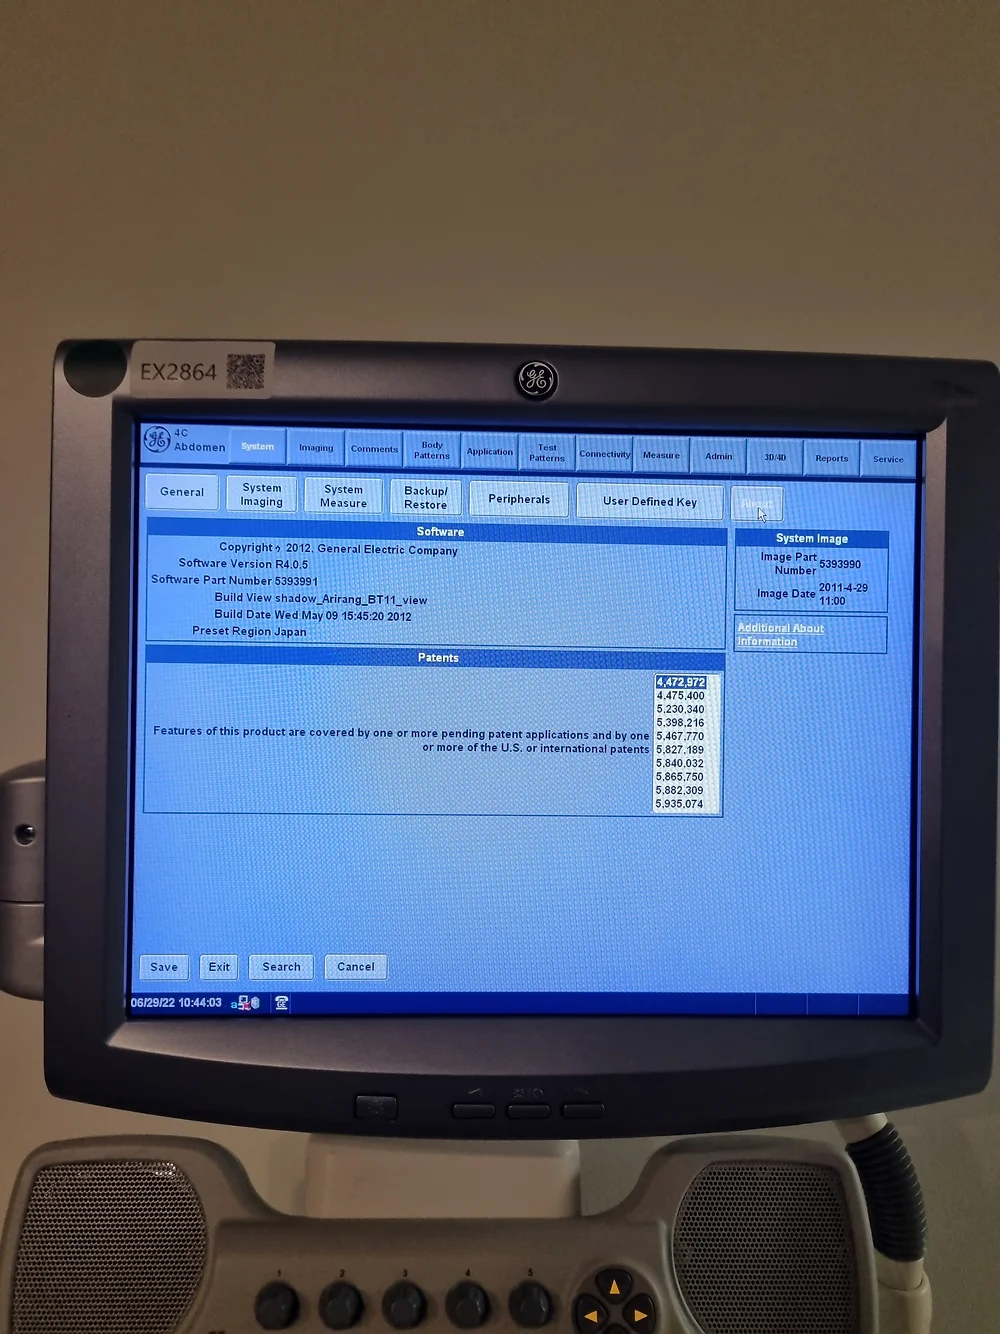

The LOGIQ P5 ultrasound system redefines compactness and efficiency while boasting a plethora of high-end features typically found in more expensive devices. Engineered for versatility and precision, this cutting-edge ultrasound scanner delivers unparalleled imaging quality across various medical specialties, including gynaecology/obstetrics, urology, cardiology, and paediatrics.

- Exceptional Performance: Despite its compact size, the LOGIQ P5 stands out as one of the most robust systems in its price range, offering features like CrossXBeam composite imaging, cardiac imaging, and speckle reduction for superior diagnostic accuracy.

- Enhanced User Experience: Navigate seamlessly through procedures with the LOGIQ P5’s intuitive interface and ergonomic design, ensuring optimal comfort and efficiency during imaging sessions.

- Comprehensive Imaging Solutions: From automatic tissue optimization to coded harmonic imaging and high pulse repetition rate, the LOGIQ P5 is equipped with a range of innovative technologies to enhance imaging performance across diverse clinical applications.